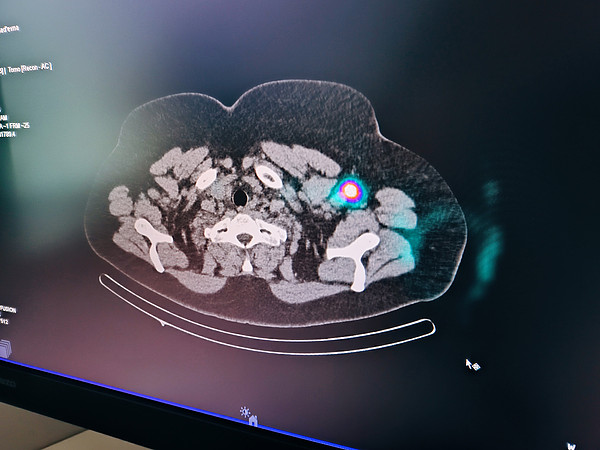

IMG_20230928_113519.